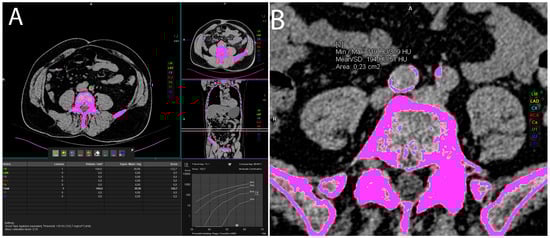

2.2. Visceral Fat Measurement

The intraabdominal visceral fat volume, expressed in cm3, was measured on the pre-contrast CT scan by manually drawing a line along the inner contour of the abdominal muscles which surround the abdominal cavity at the umbilical level. The CT value of fat tissue attenuation from −200 to −40 HU was semi-automatically segmented within the drawn line and the visceral fat volume was automatically calculated using the Siemens software syngo.via VB60A_HF08 (Figure 2).

Figure 2. Representative axial CT images showing visceral fat volume calculation (A), liver attenuation measurement (B), spleen attenuation measurement (C), and pancreas attenuation measurement (D).